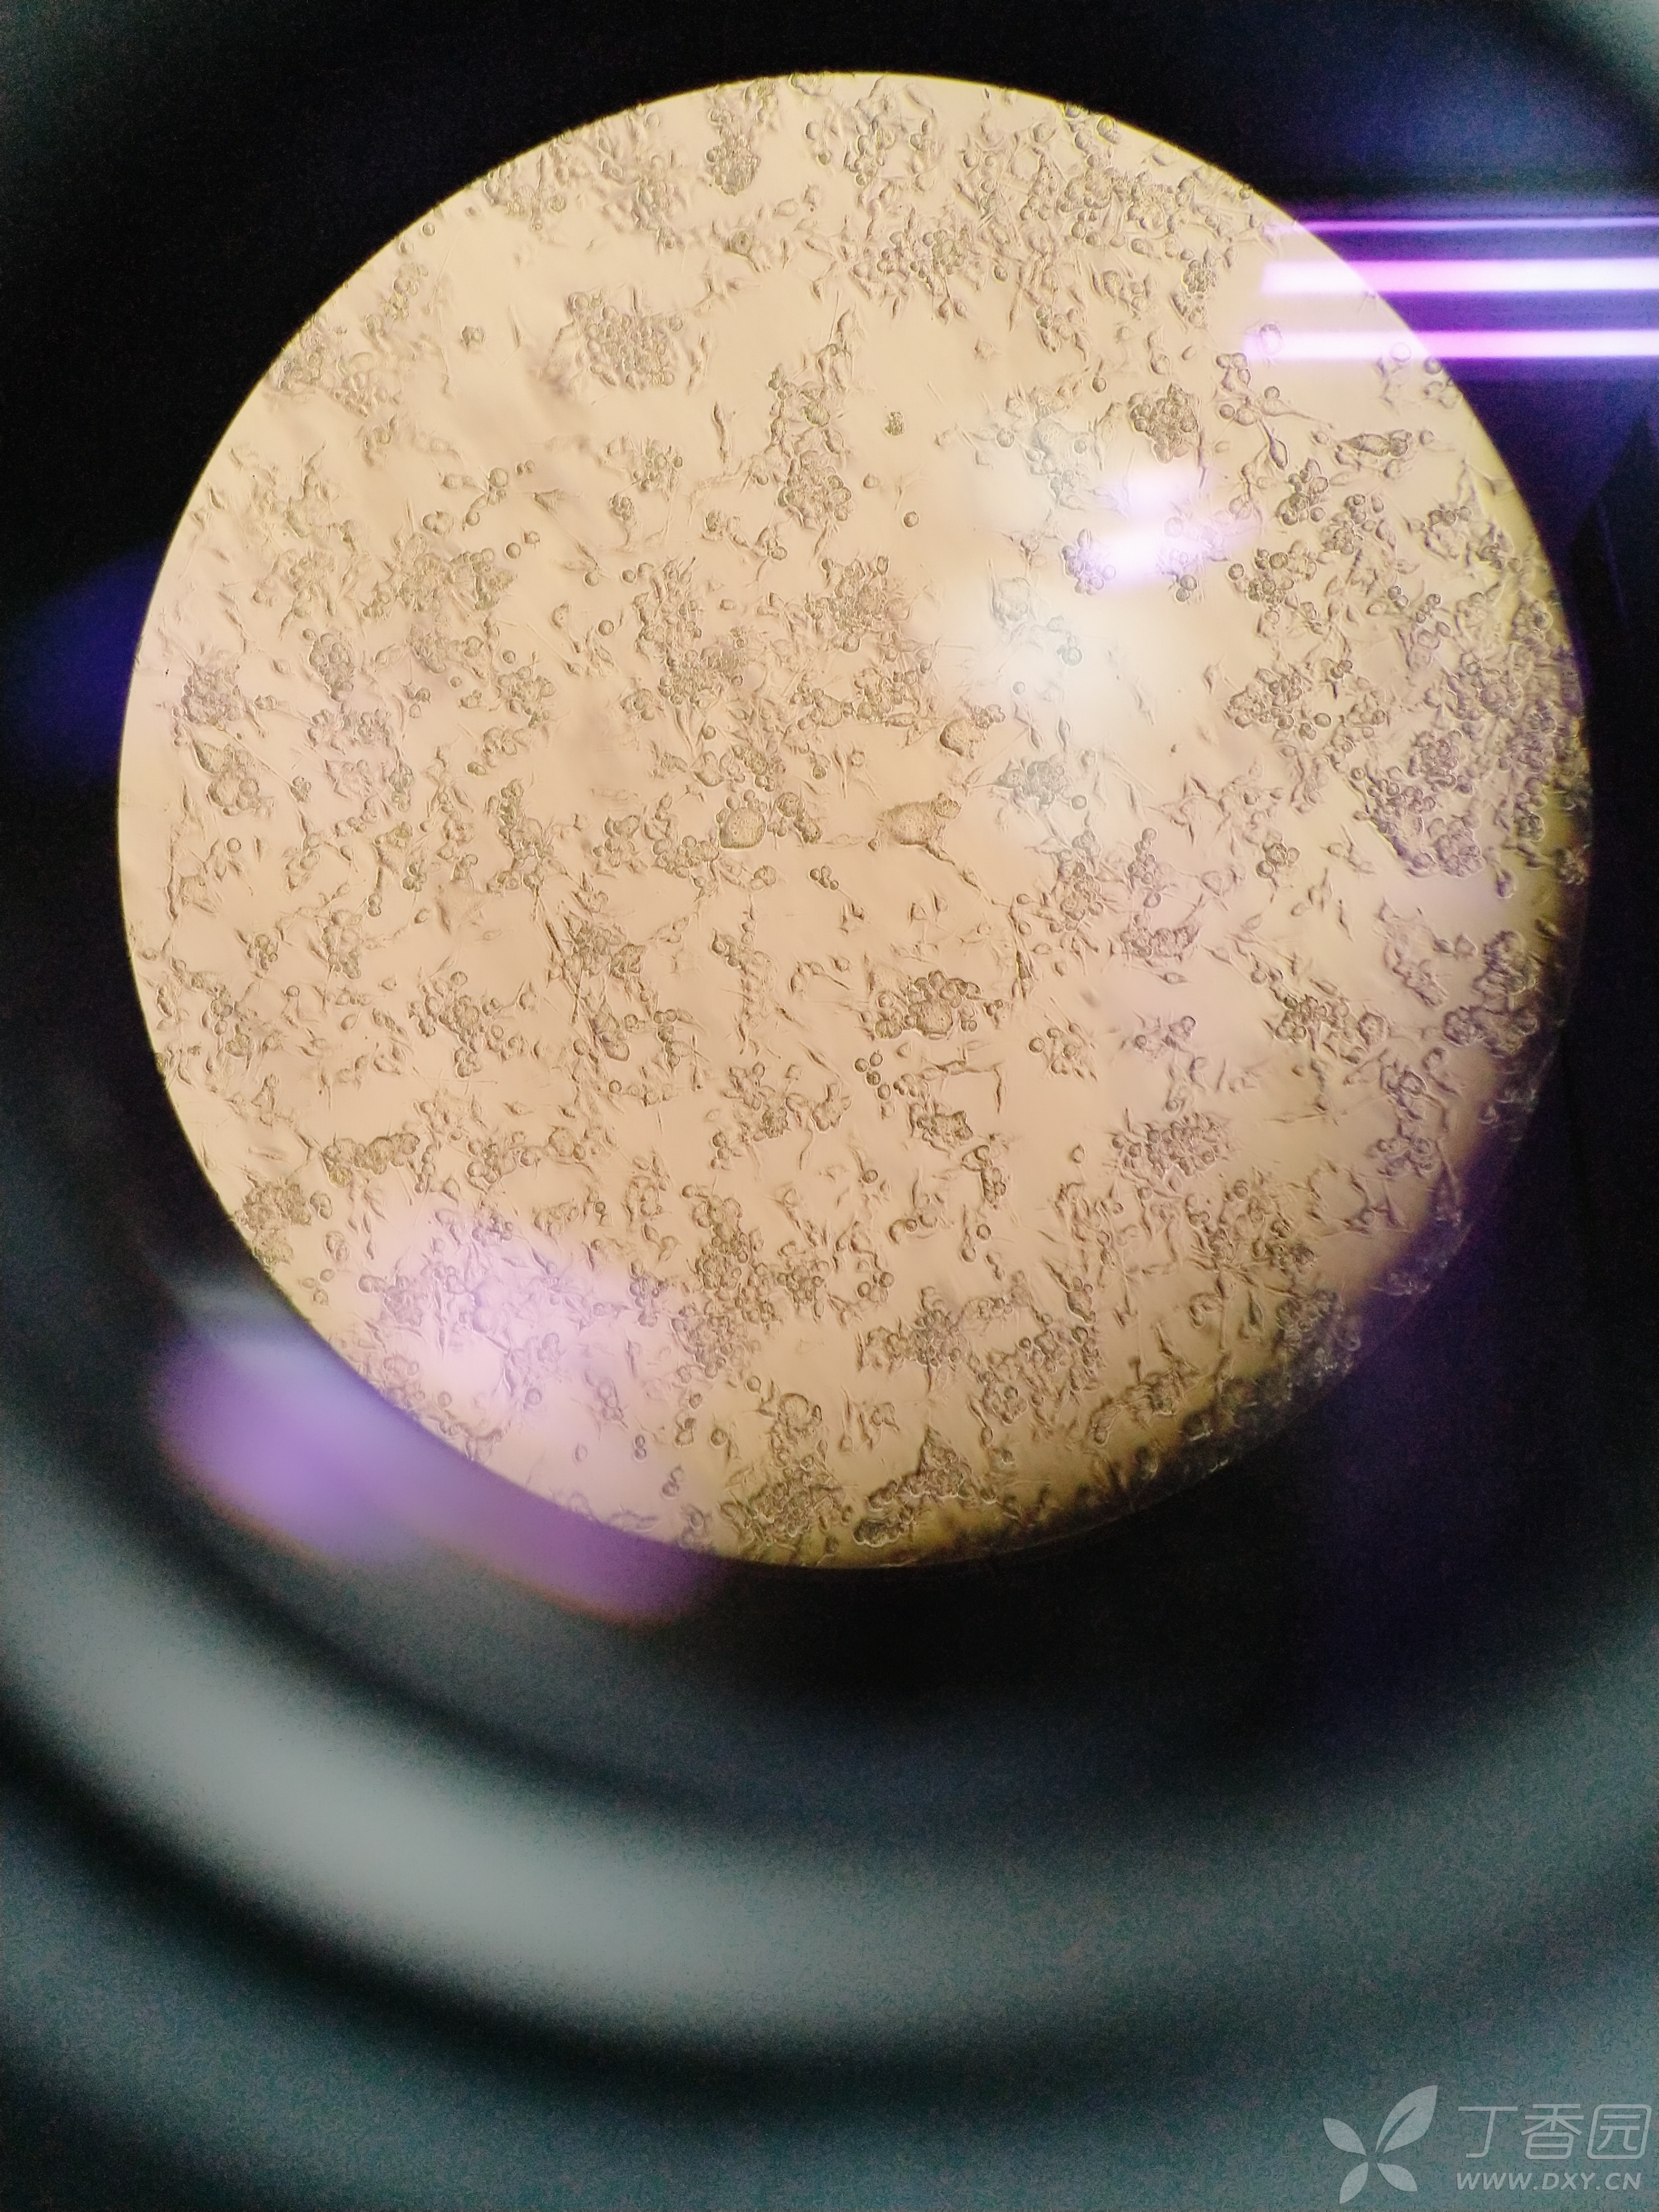

大家能不能帮我看下我的这个bv2细胞啊